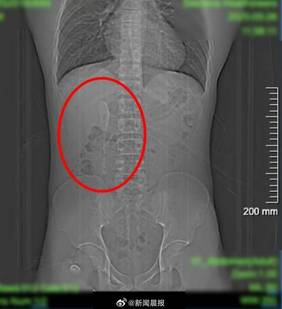

据荔枝新闻报道,近日,江苏南京,28岁小伙因腹痛就医,CT检查发现肠道内竟卡着2把勺子。

患者称是食用新疆食品时不慎吞下,起初以为只有1把,肠镜检查后确认是2把。勺子卡在回肠末端,周围黏膜已形成溃疡,随时有穿孔风险。

因异物长约12公分,且位于肠腔狭窄的小肠内,取出难度较大。医生经过近一小时操作,成功将两把勺子完整取出。医生提醒,误吞异物在临床较为常见,可能引发消化道穿孔、出血等严重后果,一旦发生需在 24 小时内及时就医处理,避免出现严重并发症。